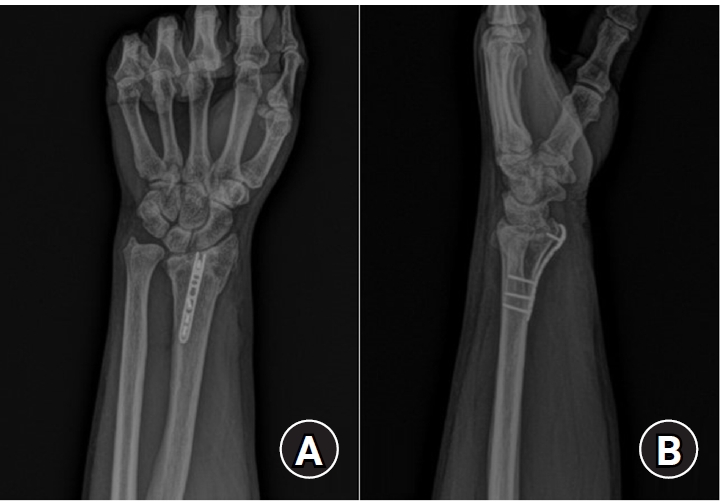

Standard anteroposterior and lateral radiographs were obtained at 2, 4, 6, and 12 weeks postoperatively to evaluate maintenance of reduction and radiographic union. At the final follow-up visit, wrist range of motion—including flexion, extension, pronation, and supination—was measured using a goniometer by an independent evaluator (Fig. 5).

Fig. 5.

Wrist range of motion—including (A) flexion, (B) extension, (C) pronation, and (D) supination—was measured at the final follow-up.

jmt-2025-00241f5.jpg

Fig. 5. Wrist range of motion—including (A) flexion, (B) extension, (C) pronation, and (D) supination—was measured at the final follow-up.